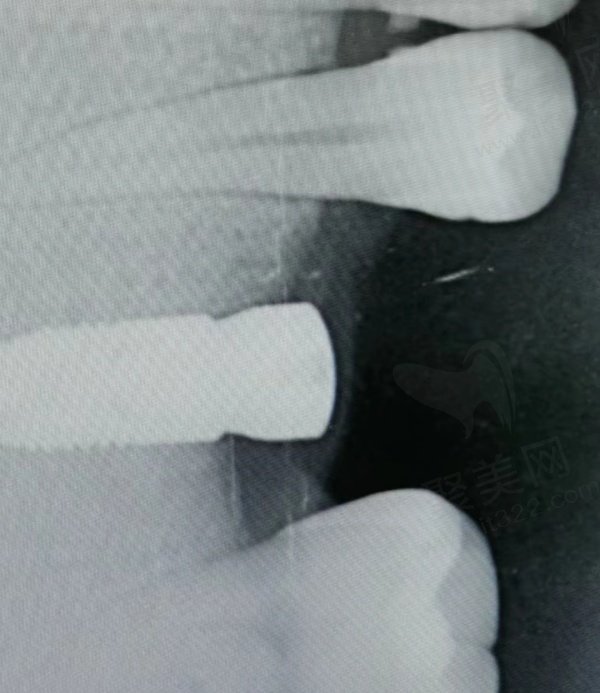

西安团圆口腔为了不断提高自己的口腔诊疗技术,引进了大量国外先进设备如:德国产CBCT数字牙科机、意大利进口全景X光机、美国产牙科CAD/CAM系统等,能够为西安广大群众带来全新的数字化诊疗体验,享受业界较为前沿的口腔诊疗技术。

网友种植牙评价1

网友种植牙评价2